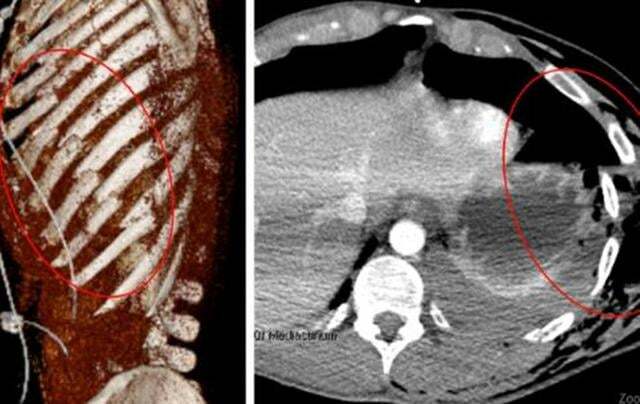

損傷類型:嚴重,例如從高處墜落,或者汽車,電動車、摩托車造成的交通事故,多為嚴重的撞擊傷。

症狀:伴有嚴重的持續疼痛,並伴有胸部壓痛、淤青和腫脹。胸部體檢可發現明顯異常。

醫生建議:需要胸部CT掃描來評估胸壁損傷和任何相關的內傷。

對於簡單、孤立,無移位的肋骨骨折,可先嘗試保守治療,必要時可採用肋間神經阻滯控制疼痛。如果保守治療無效,或者嚴重的肋骨骨折。患者隨著咳嗽出現症狀加重的表現,有的還可出現血氣胸或連枷胸等。需進行手術治療。手術適應症主要包括:肋骨骨折不癒合、胸壁畸形或缺損、導致呼吸衰竭的頑固性肋骨骨折,疼痛和連枷胸。如果需要做手術,越早效果越好。